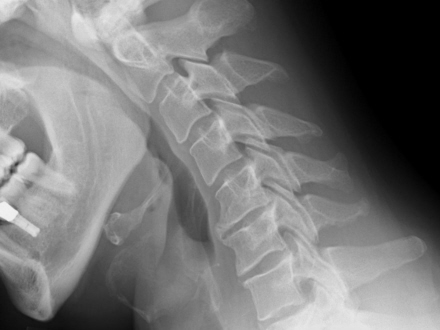

Costa del Sol sygehuset i Marbella er blevet pålagt at betale erstatning på 79.564 euro til en patient, der blev sendt hjem med en brækket nakke.

Den 48-årige bygningsarbejder havde været udsat for en ulykke i Estepona, hvor han blev ramt af to planker, der faldt ned over ham fra flere meters højde.

Manden faldt om i halv bevidstløs tilstand og kørt til en klinik i Estepona, som tilbød dækning via arbejdsgiverens privatforsikring. Manden blev bagefter overført til Costa del Sol Sygehuset, hvor en række tester og undersøgelser konkluderede, at han ikke fejlede noget. Han blev sendt hjem igen og fik besked på at gå til fysioterapi, indtil smerterne var forsvundet.

Men smerterne fortsatte, og på et tidspunkt kunne manden slet ikke bevæge den ene arm. En scanning på en privatklinik afslørede, at der var et brud i en halshvirvel efter slaget, og manden blev sendt til undersøgelse på Carlos Haya Sygehuset i Málaga, som bekræftede at, manden havde brækket nakken.

Der var imidlertid ikke meget at stille op, og den 48-årige bygningsarbejder har siden lidt af stiv nakke og kroniske smerter. Han er i dag tildelt fuld invalidepension.